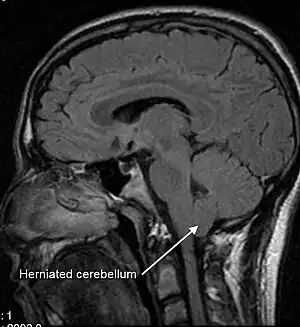

Diagnosis is made through a combination of patient history, neurological examination, and medical imaging.[20][21] Magnetic resonance imaging (MRI) is considered the preferred imaging modality for Chiari malformation.[22] The MRI visualizes neural tissue such as the cerebellar tonsils and spinal cord as well as bone and other soft tissues. CT and CT myelography are other options and were used prior to the advent of MRI, unfortunately the resolution of CT based modalities do not characterize syringomyelia and other neural abnormalities as well.[23]

By convention, the cerebellar tonsil position is measured relative to the basion-opisthion line, using sagittal T1 MRI images or sagittal CT images.[24] The selected cutoff distance for abnormal tonsil position is somewhat arbitrary, as not every person will be symptomatic at a certain amount of tonsil displacement, and the probability of symptoms and syrinx increases with greater displacement; however, greater than 5 mm is the most frequently cited cutoff number, though some consider 3–5 mm to be "borderline"; pathological signs and syrinx may occur beyond that distance.[24][25][26] One study showed little difference in cerebellar tonsil position between standard recumbent MRI and upright MRI for patients without a history of whiplash injury.[18] Neuroradiological investigation is used to first rule out any intracranial condition that could be responsible for tonsillar herniation. Neuroradiological diagnostics evaluate the severity of crowding of the neural structures within the posterior cranial fossa and their pressure against the foramen magnum. Chiari 1.5 is a term used when both brainstem and tonsillar herniation through the foramen magnum are present.[27]